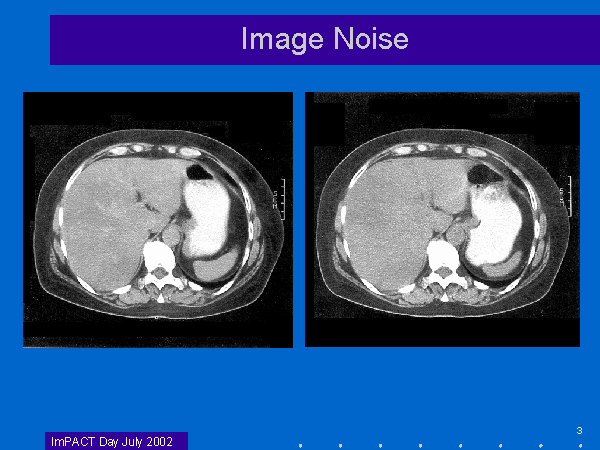

Slide 3 of 84